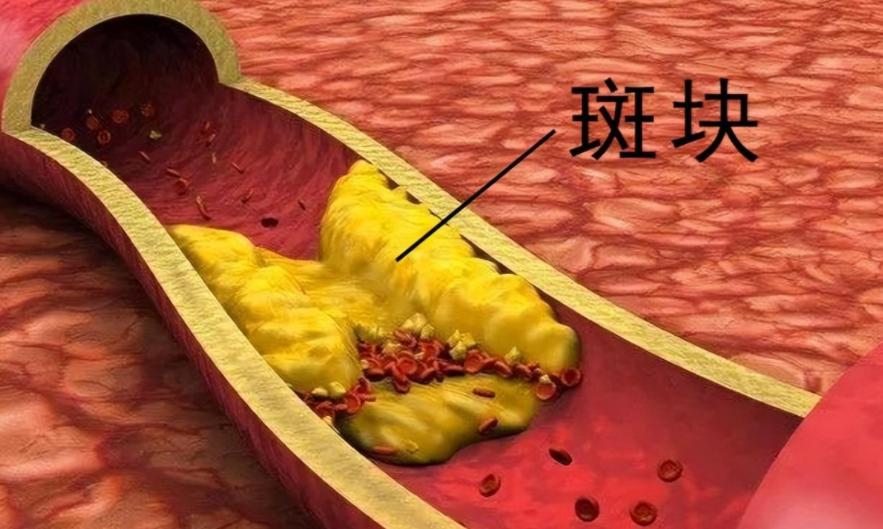

很多人以为只有高血压、高血脂才会导致脑梗。颈动脉斑块才是沉默的“定时炸弹”。它不像胸痛那样让你警觉,也不像头晕那样频繁提醒。它安静地生长,直到某天——血流被堵住,大脑瞬间“断电”。

早期斑块几乎没有任何症状。你照常上班、吃饭、刷手机,殊不知血管内壁早已布满“锈迹”。等到手脚麻木、说话不清时,黄金救治窗口可能已经关闭。这时候,后悔还有用吗?

别再迷信“多喝热水能通血管”了。真正有效的干预,从来不是靠偏方。控制血压、血糖、血脂,才是基石。尤其是低密度脂蛋白胆固醇(LDL-C),它是斑块形成的关键推手。目标值不是“正常就行”,而是要“足够低”。

值得庆幸的是,颈动脉斑块在早期是可逆的。通过严格管理危险因素,部分软斑块甚至能缩小或稳定。关键在于“早”和“坚持”。三天打鱼两天晒网,等于白干。